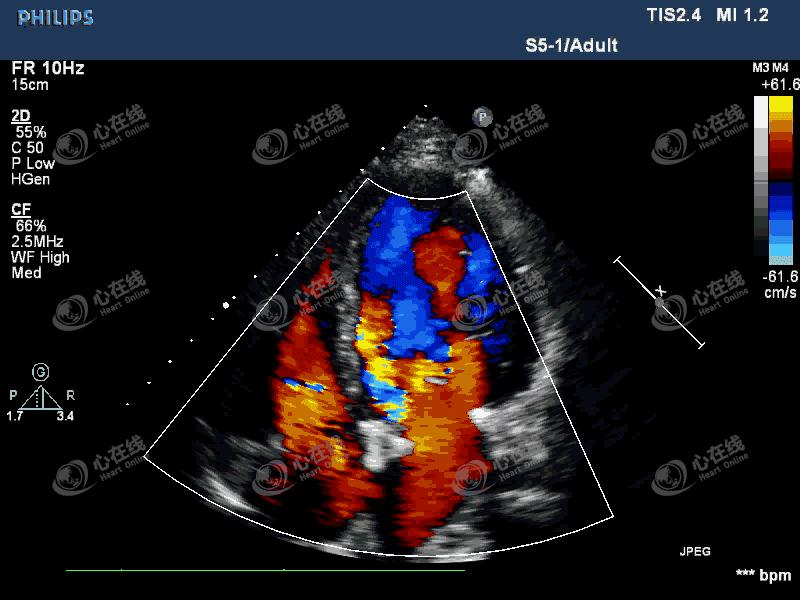

【超声心动图】

图3 四腔心切面:彩色多普勒显示中量偏心性反流信号,起自主动脉瓣机械瓣环外侧。